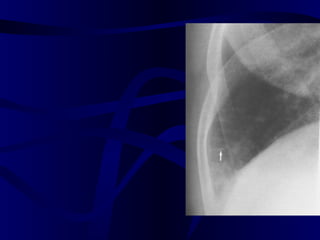

Small Pleural Effusion Normal: Sharp Angles Blunted posterior costophrenic sulcus